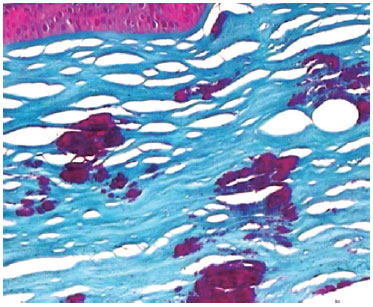

The dissected stroma was sent for anatomopathological analysis with Masson trichrome staining and showed stained hyaline deposits at various stromal layers, confirming diagnosis of GCD1 (Figure 3).

Figure 3. Anatomopathological analysis of the dissected stroma with Masson trichrome dye showing stained hyaline deposits at various stromal layers, confirming diagnosis of GCD1.

In the present study, there was no dystrophy recurrence. Instead, we found persistence of GCD1 deposits in the predescemetic layer after Type-1 Big Bubble DALK. GCD1 diagnosis was confirmed with unequivocal pathological analysis with Masson trichrome staining and topography of persistent deposits was indicated by the surgical technique (which kept the predescemetic layer intact using a Big-Bubble Type-1 technique) as well as by Visante OCT® imaging showing the persistence of deposits just anterior to the DM.